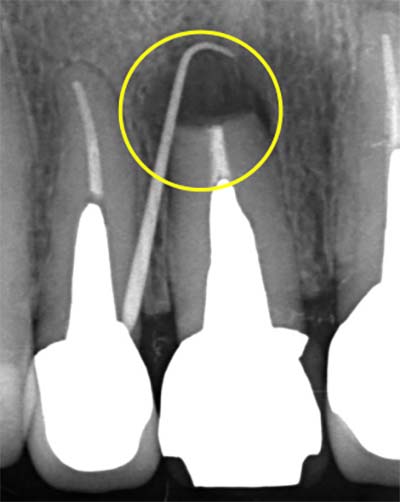

![]() |

| 術前 | 術後(封鎖) |

MTA / バイオセラミックによる3次元根尖封鎖

根の先端に行う“根尖封鎖”は、治療の成否を左右する超重要工程です。

| MTA充填前 | MTA充填後 |

MTA・バイオセラミックは、

- 封鎖性が高い

- 硬化後の安定性が良い

- 骨の治癒を促す

- 組織親和性が高い

- 再感染が起きにくい

という特徴があり、現代の根管治療のゴールドスタンダードといえます。

Torabinejad(1995)もMTAは従来材料より漏洩が極めて少ないと報告しています: